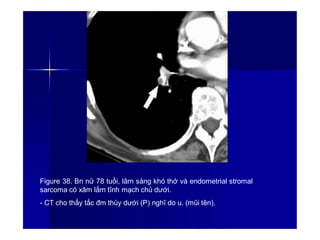

Figure 38. Bn nữ 78 tuổi, lâm sàng khó thở và endometrial stromal

sarcoma có xâm lấm tĩnh mạch chủ dưới.

- CT cho thấy tắc đm thùy dưới (P) nghĩ do u. (mũi tên).

53